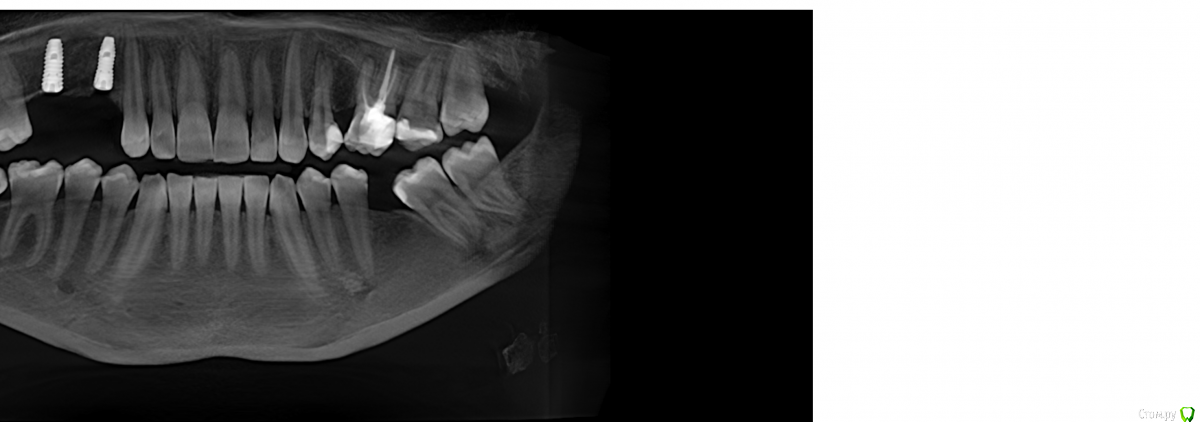

Robinbobin Опубликовано 25 марта, 2015 Поделиться Опубликовано 25 марта, 2015 Имплантаты Dio UF ll,костный материал ауто+остеоматрикс.Хотелось бы услышать мои ошибки 6 Ссылка на комментарий

red_butler Опубликовано 25 марта, 2015 Поделиться Опубликовано 25 марта, 2015 Robinbobin а зачем 1.4 так заглубили? Я бы плюсом сделал НКР на оба винта Ссылка на комментарий

Robinbobin Опубликовано 25 марта, 2015 Автор Поделиться Опубликовано 25 марта, 2015 Robinbobin а зачем 1.4 так заглубили? Я бы плюсом сделал НКР на оба винта Читал что шурупы конусные нужно заглублять,а нкр зачем?дефицита кости с вестибулярной стороны нету же вроде 1 Ссылка на комментарий

колесников Опубликовано 25 марта, 2015 Поделиться Опубликовано 25 марта, 2015 Вестибулярная компактная пластинка резорбируется на 3 мм у шеек имплантов. Вы конечно оставили дополнительно остеоматрикс вестибулярно ? В области 14 обязательно подсадите стт, можно на этапе формирователя. 16 можно было и короче взять,тогда бы он целиком находился в материале. А в целом Всё достойно. Ссылка на комментарий